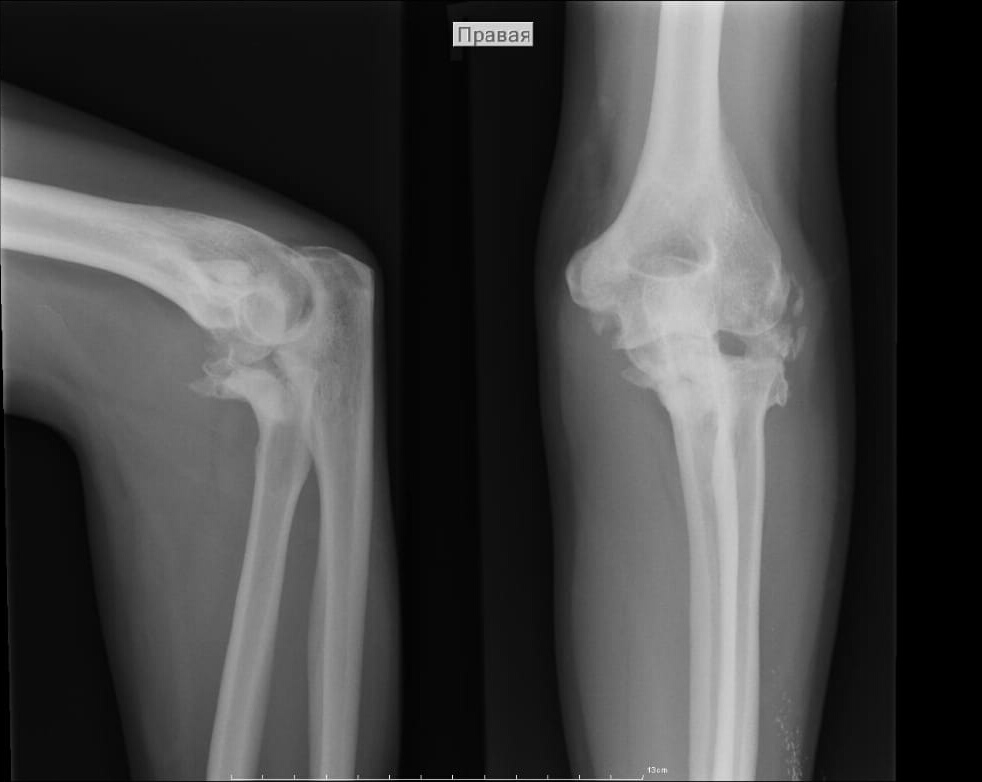

п÷п╟я├п╦п╣п╫я┌я┐ 38 п╩п╣я┌. п╒я─п╟п╡п╪п╟ п╡ я│п╣п╫я┌я▐п╠я─п╣ 2017 - п╡я▀п╡п╦я┘ п╩п╬п╨я┌п╣п╡п╬пЁп╬ я│я┐я│я┌п╟п╡п╟ я│

п╥п╟п╨я─я▀я┌я▀п╪ п╬я│п╨п╬п╩я▄я┤п╟я┌я▀п╪ п©п╣я─п╣п╩п╬п╪п╬п╪ пЁп╬п╩п╬п╡п╨п╦ п╩я┐я┤п╟. п▓ п╬п╢п╫п╬п╧ п╦п╥ п╠п╬п╩я▄п╫п╦я├ п°п╬я│п╨п╡я▀

п©я─п╬п╦п╥п╡п╣п╢п╣п╫п╬ п╡п©я─п╟п╡п╩п╣п╫п╦п╣ п╡я▀п╡п╦я┘п╟, я─п╣п╥п╣п╨я├п╦я▐ пЁп╬п╩п╬п╡п╨п╦ п╩я┐я┤п╟. п≤п╪п╪п╬п╠п╦п╩п╦п╥п╟я├п╦я▐ пЁп╦п©я│п╬п╪

п╩п╬п╨я┌п╣п╡п╬пЁп╬ я│я┐я│я┌п╟п╡п╟, п©п╬ я─п╣п╨п╬п╪п╣п╫п╢п╟я├п╦п╦ п╨п╩п╦п╫п╦п╨п╦